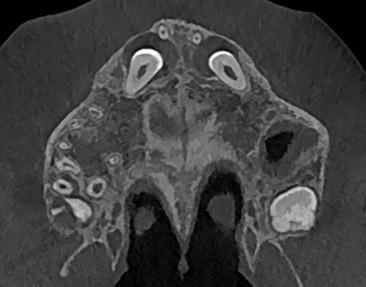

CBCT szczęki

Zęby 13, 23 położone skośnie, mezjalnie i podniebiennie.

Korony zębów otoczone szerokimi mieszkami – ok 10-12mm - mogą odpowiadać torbielom zawiązkowym.

Korzenie proste, wierzchołki z niezakończonym rozwojem.

W łuku zębowym zęby mleczne 53, 63.

Położenie koron zębów 13,23 podniebienne względem korzeni zębów 12, 22.

Widoczna resorpcja korzeni siekaczy bocznych na długości 1/3 wierzchołkowej korzeni.

12 powyżej 13

22 powyżej 23